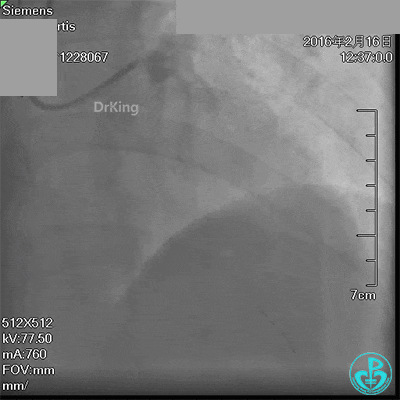

送入CCU观察,术后2小时感咽部不适,伴胸部胀痛、气促。立即复查心电图见有动态变化,床边超声检查未见心包积液,即刻予以替罗非班静脉泵入,吗啡镇痛,持续静脉水化等处理,患者症状无明显缓解,诉胀痛及气促有加重趋势,伴咳嗽。行胸部CT平扫发现纵隔血肿。

急诊术中导丝在锁骨下通过困难,曾在局部推注造影剂造影,回顾造影结果发现局部小血管破裂造影剂渗漏。